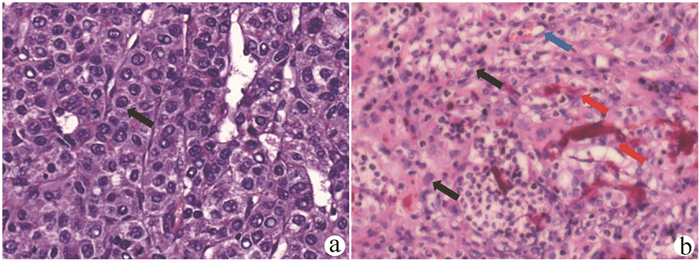

Liver biopsy diagnosis of hepatic extramedullary hematopoiesis: A case report

Lilin JIANG, Juanjuan FU, Linxin TANG, Zhi WANG, Zhonghua LU

2021, 37(11): 2644-2645. DOI: 10.3969/j.issn.1001-5256.2021.11.031

Abstract(1162) HTML (543) PDF (2617KB)(82)